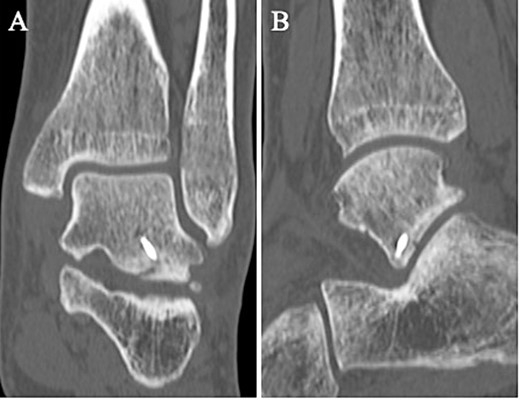

A 24-year-old male basketball player presented to our hospital complaining of left lateral ankle pain during a cutting motion. His height, weight, and body mass index were 172 cm, 64.0 kg, and 21.6 kg/m2, respectively, and he had no history of previous medical conditions. On his first visit to our hospital, he could not walk due to pain. Physical examination revealed swelling, ecchymosis, and tenderness at the lateral aspect of his left ankle. The American Orthopedic Foot and Ankle Society (AOFAS) score was 32 out of 100 points. Plain radiographs of the left ankle showed no abnormal findings in the anteroposterior view, but a fracture line was discovered at the base of the lateral process of the talus in the lateral view (Fig. 1). Non-contrast computed tomography (CT) showed a simple fracture line that extending from the talofibular articular surface down to the posterior talocalcaneal articular surface of the subtalar joint. In addition, the bone fragment was displaced >2 mm (Fig. 2). The patient was diagnosed with Type I LPFT and underwent surgical treatment.

Non-contrast CT showed a simple fracture line that extending from the talofibular articular surface down to the posterior talocalcaneal articular surface of the subtalar joint in the coronal (A) and sagittal (B) views.

Postoperatively, a non-weightbearing short leg splint was postoperatively applied for 2 weeks. Active and passive range of motion exercises of the ankle were permitted at 2 weeks postoperatively. Partial-weightbearing was allowed at 4 weeks postoperatively, and full-weightbearing at 6 weeks postoperatively. The patient was allowed to jog 8 weeks after surgery. After confirming that bone union was obtained on non-contrast CT (Fig. 5) and tenderness on the lateral side of the ankle had resolved, the patient was allowed to return to his original sport at 12 weeks postoperatively. Two years after surgery, the patient remained a competitive basketball player with no symptoms. Additionally, the AOFAS score had improved to 100 points.

A non-contrast CT taken at 12 weeks postoperatively showed bone union in the coronal (A) and sagittal (B) views.